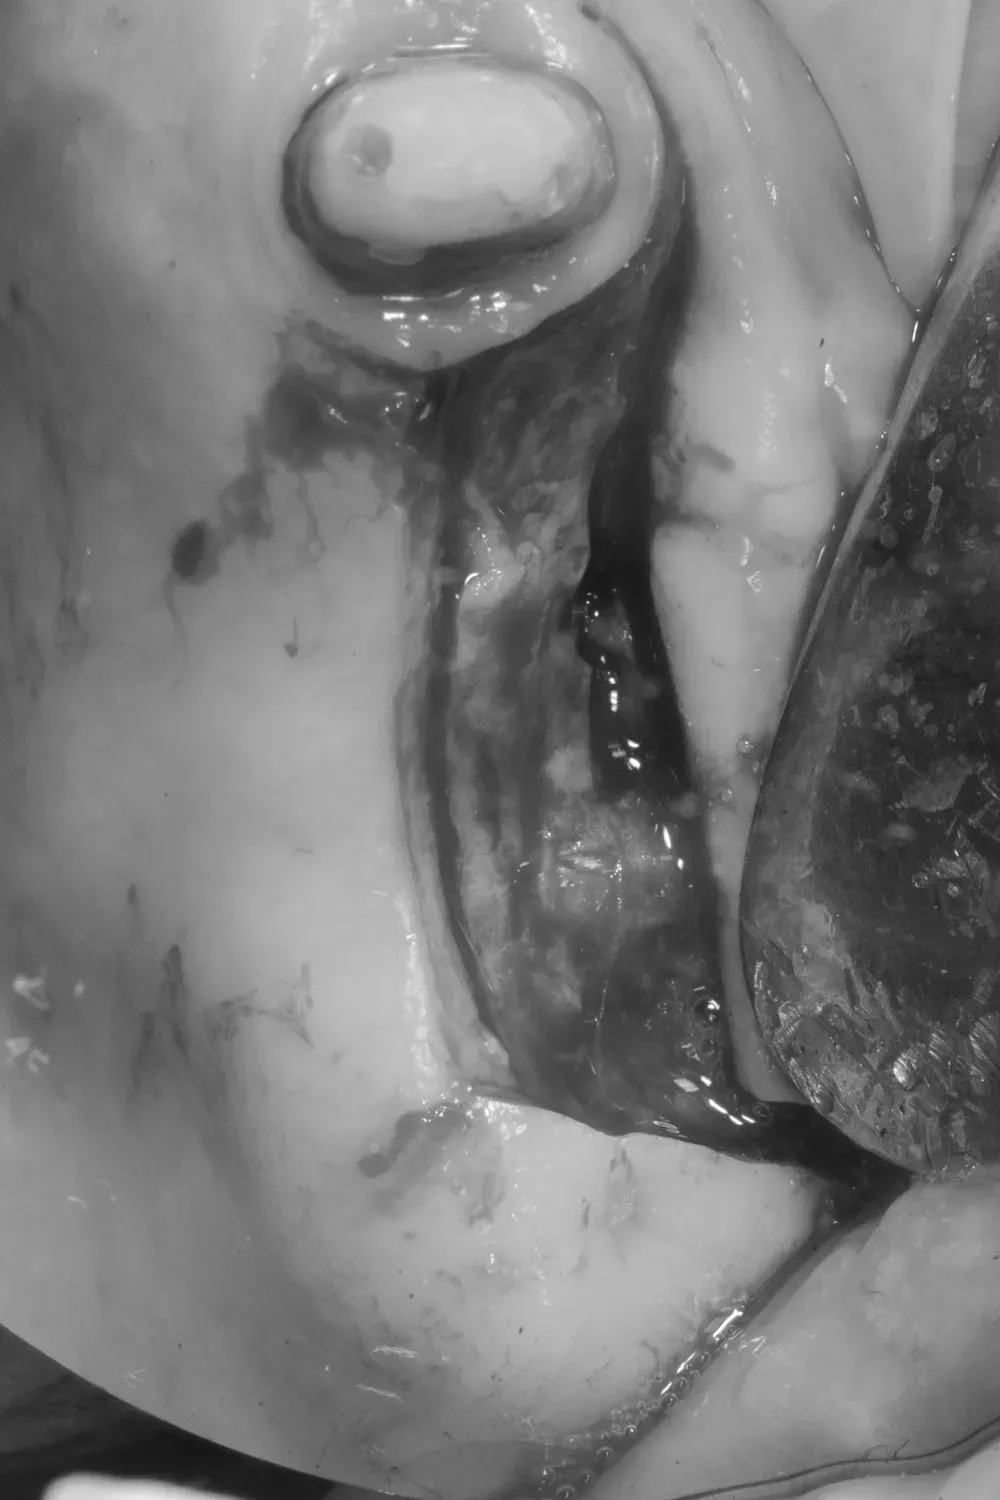

Sul lato sinistro, l’atrofia dopo la rimozione dei denti e la rigenerazione era comunque meno grave e rientrava nell’ambito delle categorie S1-S2 CCARD. La prossima immagine è la CBCT della zona mascellare sinistra prima delle estrazioni.